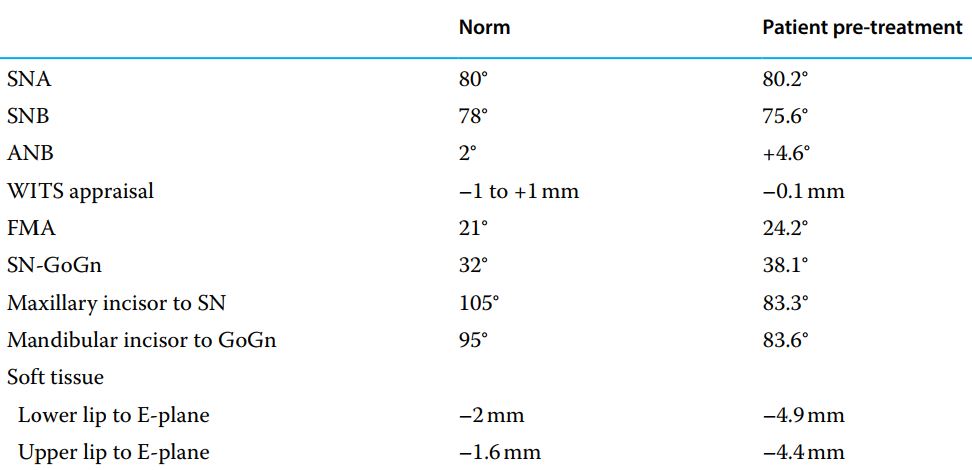

Nền xương hạng I, góc mặt phẳng hàm dưới hơi mở, trục răng cửa hàm trên và hàm dưới dựng đứng, cắn sâu và chen chúc răng cửa dưới.

Mục tiêu điều trị bao gồm nới rộng cung răng kèm thêm mài kẽ (nếu cần), giải cắn sâu và sắp đều răng.

Đặt thun tách kẽ trước đó 1 tuần, sau đó thử khâu và làm khí cụ Quad-helix.

Hai tuần sau, kích hoạt và gắn Quad-helix. Gắn mắc cài lên các răng còn lại hàm trên (ngoại trừ răng sữa và R12 chưa mọc đủ, R23 còn lệch cao), đi dây 016 NiTi, đặt lò xo đóng từ R4 đến răng cửa mỗi bên.